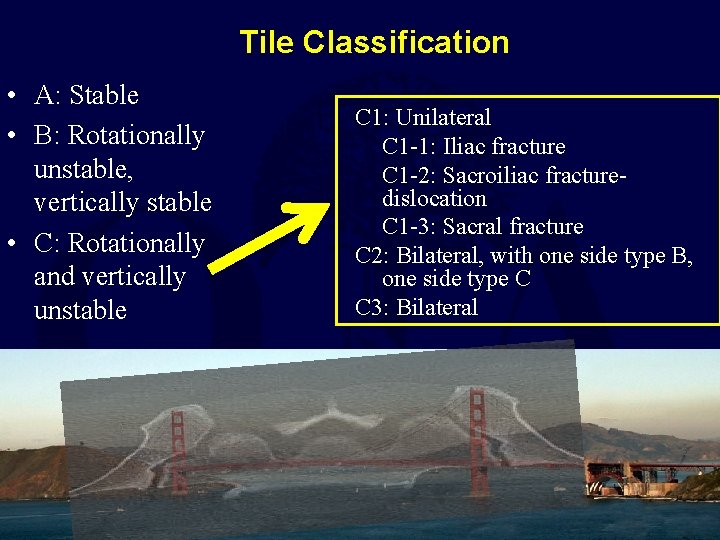

Tile Classification A: Stable • Based on cadaveric sectioning • Posterior ring only! } B: Partially stable C: Completely unstable

Tile Classification • A: Stable • B: Rotationally unstable, vertically stable • C: Rotationally and vertically unstable A 1: Avulsion injury A 2: Iliac wing or anterior ring from direct blow A 3: Transverse sacrococcygeal fracture

Tile Classification • A: Stable • B: Rotationally unstable, vertically stable • C: Rotationally and vertically unstable B 1: Open book (external rotation) B 2: Lateral compression injury (internal rotation) B 2 -1: Ipsilateral anterior and posterior injuries B 2 -2: Contralateral (buckethandle) injuries B 3: Bilateral

Tile Classification • A: Stable • B: Rotationally unstable, vertically stable • C: Rotationally and vertically unstable C 1: Unilateral C 1 -1: Iliac fracture C 1 -2: Sacroiliac fracturedislocation C 1 -3: Sacral fracture C 2: Bilateral, with one side type B, one side type C C 3: Bilateral